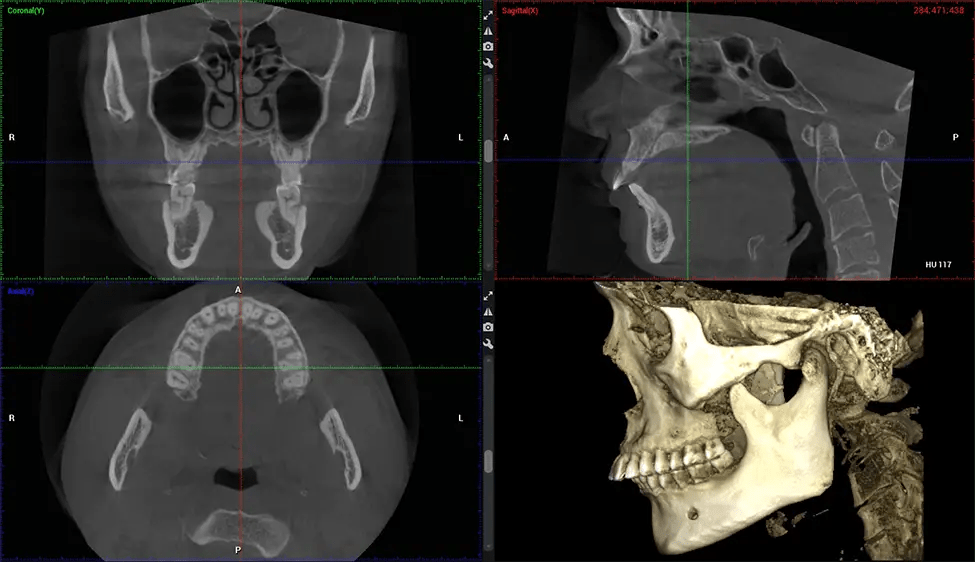

Cone Beam Computed Tomography (CBCT) is an advanced imaging technique used in dentistry and maxillofacial surgery to obtain detailed 3D images of the oral and maxillofacial structures. At Dr G Dental Studio, our CBCT scanners utilize a cone-shaped X-ray beam and a specialized detector to capture images from different angles. A computer then combines these images to create a 3D representation of the patient’s oral anatomy.

This 3D scan, called cone beam computed tomography, gives your dentist a more complete image of your oral anatomy and disease processes than a traditional X-ray. Unlike conventional X-rays, which capture a 2D image of your mouth from various angles, a 3D scan takes multiple digital X-rays for one image. It provides a complete view of your jaw, teeth, nerves, and soft tissues. This enhanced view allows dentists to detect minor issues not visible in traditional 2D scans, such as impacted wisdom teeth or bone fractures in the sinus cavity.

There are many benefits to using CBCT technology, especially compared to the traditional 2D X-ray format. One of the most significant advantages of CBCT scans is that they provide much more information than traditional X-rays. A scan lets your dentist see images from all angles of your jaw and mouth, including your sinuses, nasal cavity, cheekbones, and other surrounding areas. This added information helps your dentist craft a comprehensive treatment plan that addresses all aspects of your oral health.

After the scanning process, the captured X-ray images are processed by the CBCT software, which applies algorithms to reconstruct a detailed 3D image of the scanned area. The software compiles these individual X-ray images and creates a digital 3D representation of the patient’s anatomy. The reconstructed 3D CBCT image can be viewed and analyzed by the dentist or radiologist. This image can be manipulated, rotated, and zoomed in or out to examine specific structures and evaluate the patient’s condition.